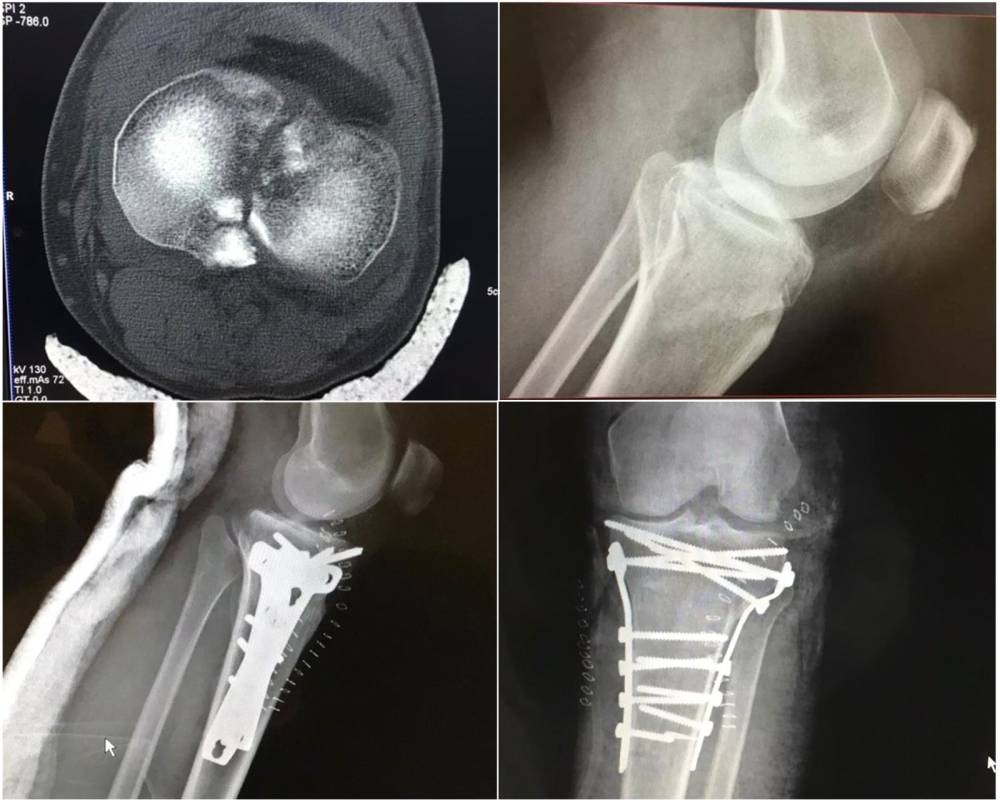

تمكن مستشفى الأفلاج العام عضو تجمع الرياض الصحي الأول في تثبيت كسر مفتت من الدرجة الخامسة في أعلى قصبة الساق اليسرى؛ لمصاب في العقد الرابع من عمره تعرض لحادث دهس.

وقام الفريق الطبي برد مفتوح وتثبيت داخلي تحت التخدير النصفي للمريض، وتم الاسترداد التام للسطح المفصلي لمفصل الركبة اليسرى، مع إصلاح قطع الرباط الجانبي الداخلي فيها.